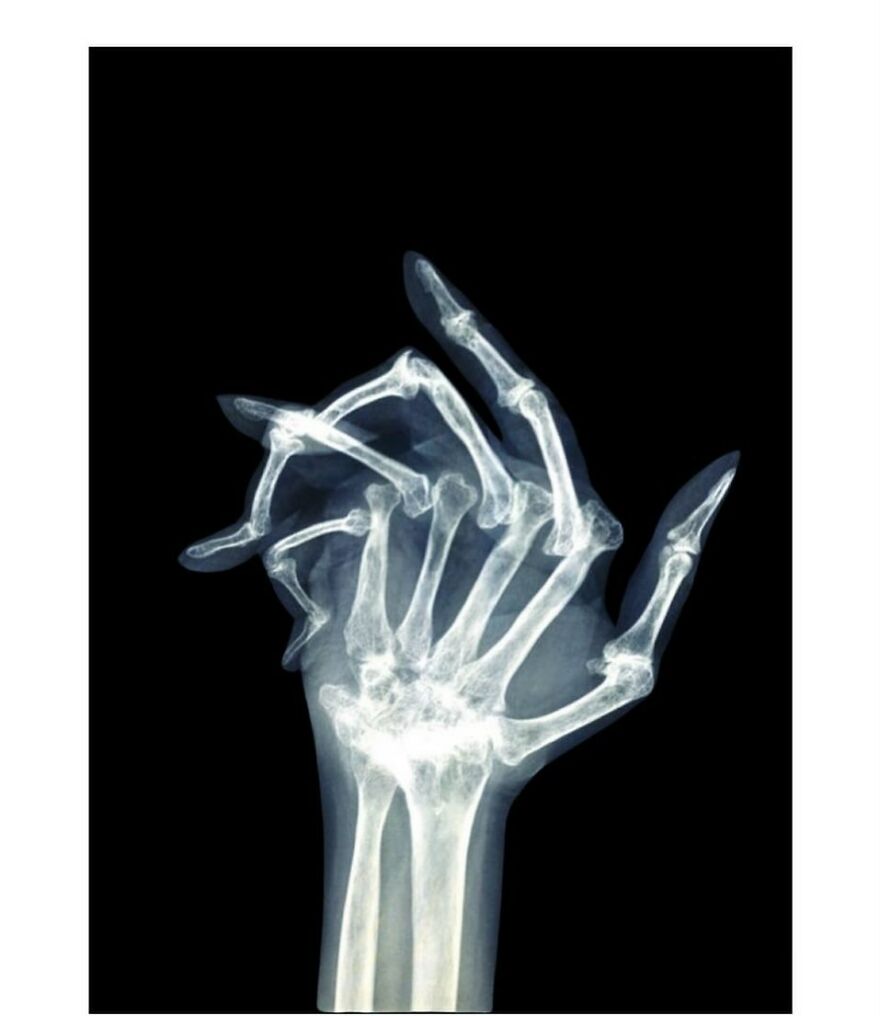

Rheumatoid arthritis. My mom had it, she passed in Jan 2024 from complications of it. (calcified heart valve, heart attack). What people dont understand is that RA ravages so many different things in a body. My mom had 2 bone infections from it that required PIQ lines, no immune system, several blood transfusions (never found what caused the loss), had the calcified valve replaced prior to calcification, just so many odd things that seem unrelated. Yet she never complained. She was more frustrated w the loss of her independence. RIP Mom, you are a legend amongst those who knew you and I miss you everyday and i will miss you till we see eachother on the next adventure.